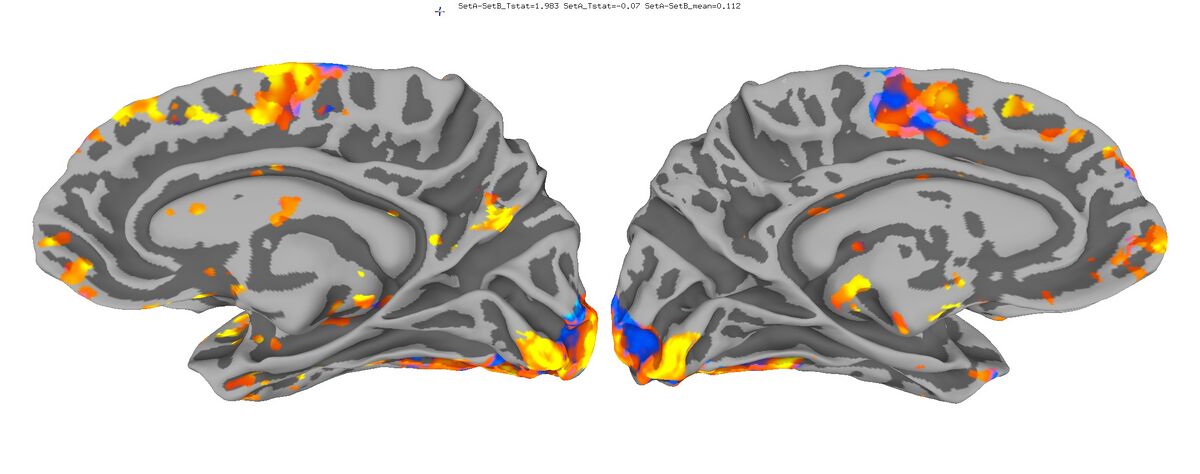

Functional Data

Functional data of the Mouth vs. Eye contrast mapped to the average surface. It is hard to quantify the difference, but one way is to compare the maximum statistical values; with better intersubject alignment, these would presumably increase.

1. NEW: Max t-value for Mouth: 9.3 Eye:10.1 Eye vs Mouth: 5.6

2. OLD: Max t-value for Mouth: 7.9 Eye:8.8 Eye vs Mouth: 5.8

New